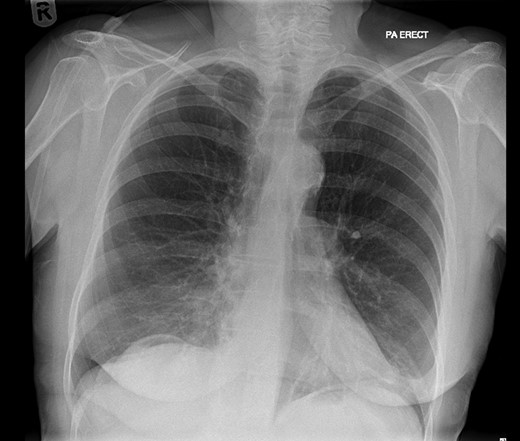

On examination, she was febrile. Her abdomen was generally tender. Bowel sounds were present and up to that time her stoma was working. Her perineal hernia was red and tender. Her initial CXR (Fig. 1) did reveal a sliver of gas underneath her right hemidiaphragm and in keeping with her abdominal findings she progressed to further imaging. CT abdomen pelvis with contrast showed pneumoperitoneum (Fig. 2) with ‘a tiny pocket of air is also seen adjacent to a loop of bowel in the pelvis posterior to the bladder’. ‘Exact site of perforation has not been demonstrated but could possibly be in the bowel loops in the perineum’ (Figs 3 and 4).